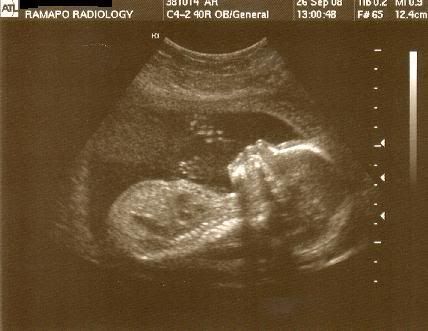

So, everything went very well with my little 's anatomy scan! He was wiggling up a storm. My Mom and Stepdad got to come in and see him too. Every organ and system is developing perfectly and he appears to be happy and healthy with 10 fingers and 10 toes! He's also measuring right on schedule.

So, without further adieu....here's my baby at almost 20 weeks (19 Weeks, 6 Days)